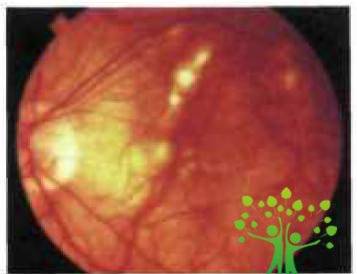

Транссудативная, или «влажная», форма ЦХРД при миопии встречается значительно реже, чем «сухая» однако характеризуется относительно ранним началом н тяжелым течением и сопровождается резкой внезапной потерей зрения. Патогенетическую основу этой формы макулодистрофии составляют хориоретинальные изменения с повреждением мембраны Бруха и в части случаев с развитием субретинальной неоваскуляризации. Наиболее частой формой транссудатов ной миопической макулодистрофии является геморрагическая (рис. 4).

Клиническая картина осложненной близорукости

Рис. 4. Геморрагическая форма центральной хориоритенальной дистрофии: формирующаяся неоваскулярная мембрана(www.glazmed.ru)

Различают два основных патогенетических типа кровоизлияний при миопии: связанные с разрывами стекловидной пластинки (формирование так называемых лаковых трещин — ЛТ) без неоваскуляризации и связанные с формированием субретинальной неоваскулярной мембраны.[11]

Кровоизлияния первого типа могут встречаться у молодых пациентов, а также у детей и подростков с врожденной или, реже, рано приобретенной миопией и быть одним из ранних признаков ее осложненного течения. Они имеют вид единичных или множественных темно-красных округлых пятен с четкими контурами, как правило, небольшого размера: от точечных до ¼ диаметра диска (ДД). Их нередко называют монетовидными. Они располагаются в наружных (глубоких) слоях сетчатки, где аксоны располагаются перпендикулярно поверхности мембраны Бруха. В этих слоях экстравазация крови имеет дискретную локализацию, поскольку элементы крови разгорожены окружающими аксонами.[12]